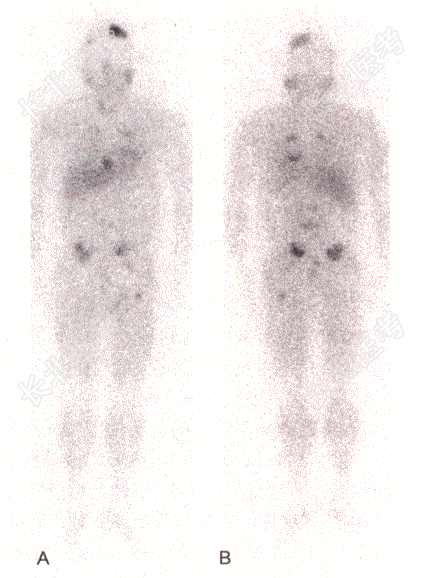

- [材料题] 患者,男,62岁,发作性头痛、心悸、手抖、大汗、呕吐2年余;24h尿儿茶酚胺明显升高。CT示多发骨转移。14年前于外院行左侧肾上腺嗜铬细胞瘤切除术;术后仍有高血压。 肾上腺髓质显像:全身显像示头部、胸部、腹部可见多个大小不等、形状不一的异常放射性浓聚区。